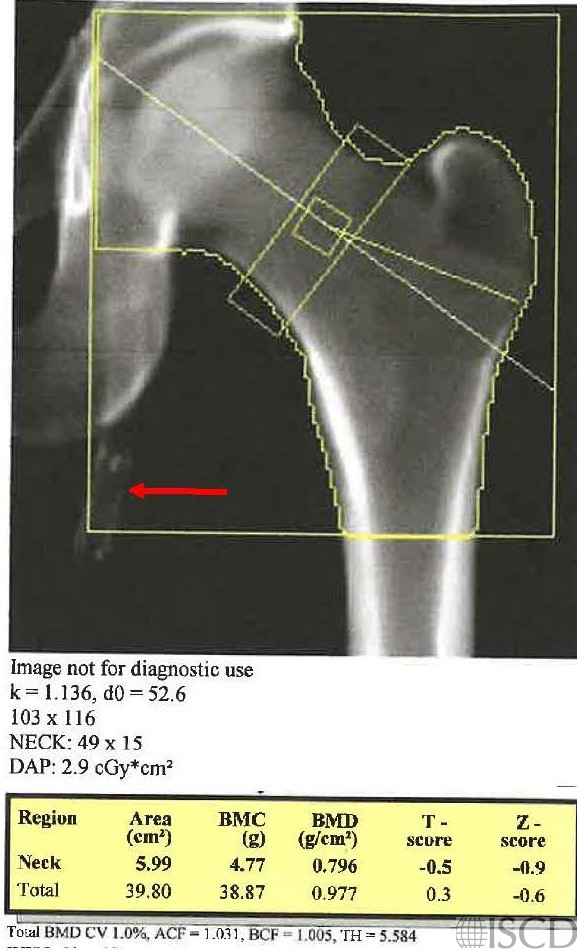

There is a left femoral stent/graft seen on the left Hologic hip scan.

The accompanying radiograph shows the stent/graft.

There is a left femoral stent/graft seen on the left hip DXA. The accompanying radiograph also demonstrates the stent/graft. The stent/graft would be removed by the software from the soft tissue baseline. On a Hologic machine, the undo view may be checked to confirm that it is removed from the soft tissue baseline.